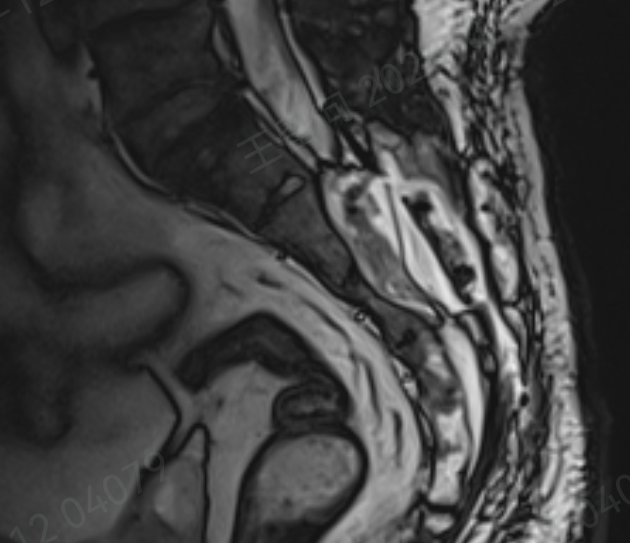

针对刘先生的病情,团队经过详细评估,制定了个性化手术方案。手术中,孙红山在显微镜和神经电生理监测下,精准找到囊肿内微小的脑脊液漏口,取刘先生自身的脂肪组织填塞漏口,随后分离囊壁并缩窄缝合,重建神经根袖,外部再用人工硬膜加固。

同时,术中采用超声骨刀完整切除骶板,术后还原固定,实现原有解剖复位。

整个手术过程都在神经电生理监测下进行,能最大程度保护骶神经,避免出现大小便障碍、肢体感觉或活动异常等并发症。

这种 “漏口封堵 + 囊腔缩窄填塞”的手术方式,既彻底解决了脑脊液漏的问题,又能保留正常神经功能,术后囊肿会自然消失,治疗效果更精准、更安全。

术后复查显示,刘先生的脑脊液漏已完全封堵,骶管囊肿未再复发,也没有出现任何并发症。